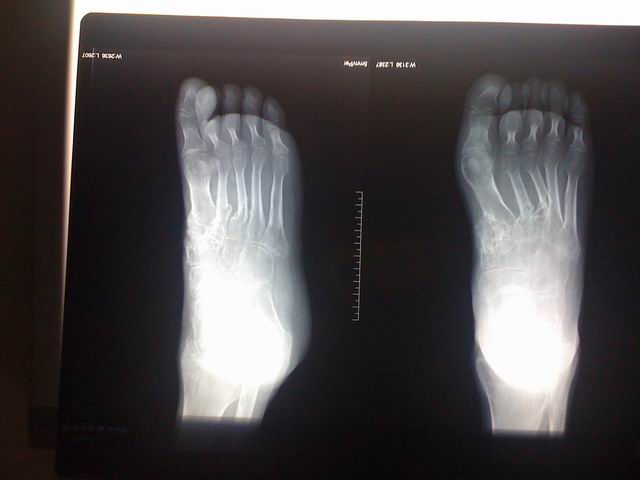

宗亲们好,这是过来拍的片子。

调整大小 IMG_0031.jpg

调整大小 IMG_0032.jpg

调整大小 IMG_0033.jpg